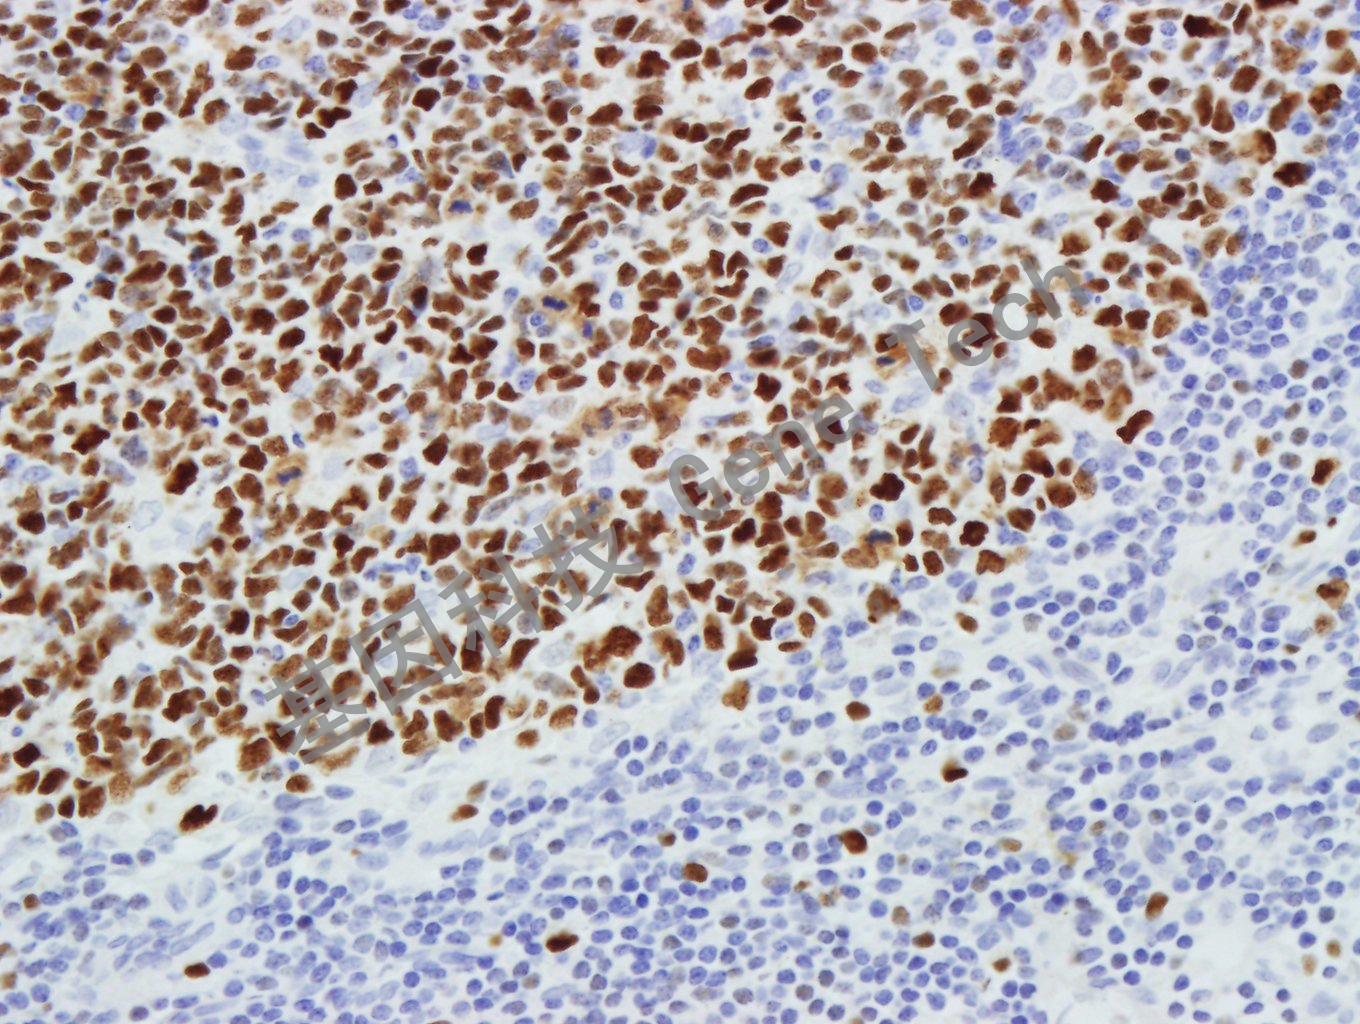

| 預處理:高pH熱修復 | 陽性部位:細胞核 | 陽性對照:結腸 |

| 扁桃體石蠟切片,用 MCM3(GT2279)染色,細胞核陽性,DAB 顯色。 | ||